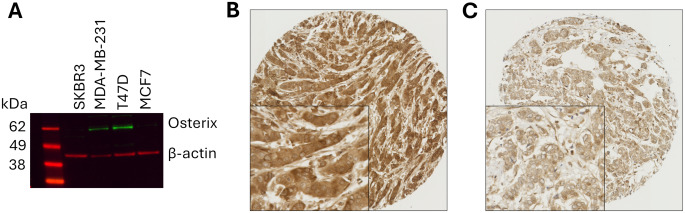

Methods: Osterix protein expression was evaluated in 1340 early-stage invasive breast tumours by immunohistochemistry. Cytoplasmic and nuclear expression levels were assessed and associations with clinicopathological variables and patient survival determined. Additionally, SP7 mRNA expression was examined in the METABRIC cohort of patients. Gene set enrichment analysis (GSEA) was performed to explore the role of osterix in the hallmarks of cancer genesets.